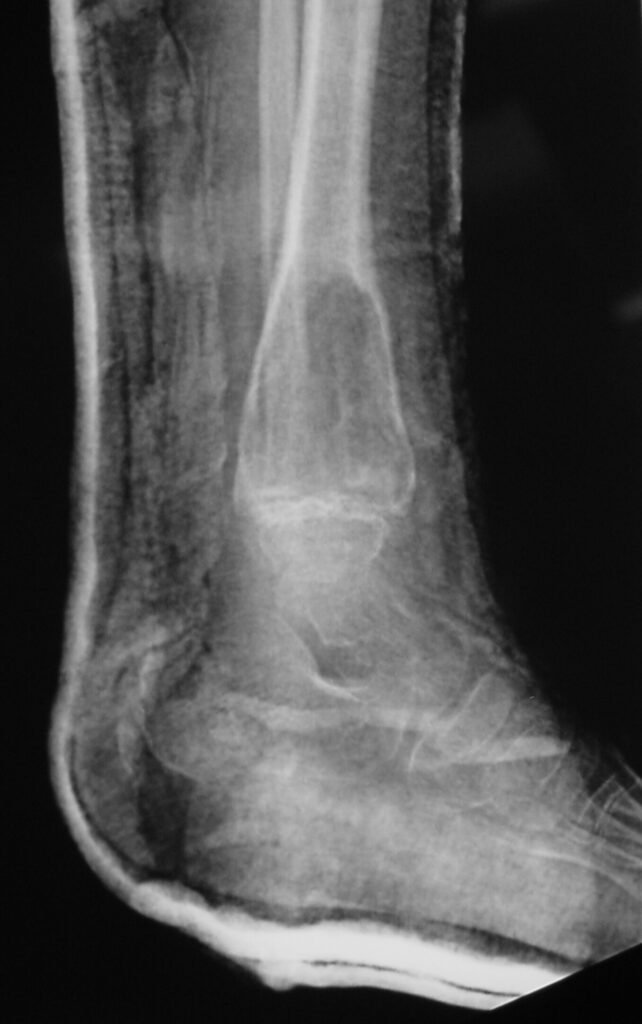

Plain x-ray

• Radiolucent

• Geographic and Eccentric lesion that is well circumscribed

• May scallop or expand the surrounding cortex

• Surrounded by sclerotic bone

• Methaphyseal region most common

• Eccentric

• Elevation of the periosteum could be seen as a benign appearing periosteal reaction (continuous periosteal reaction)

Fig 1a. Plain X-ray (AP View). ABC of the Distal Tibia: Geographic Well Circumscribed Lesion in the distal tibia. The cortices are expanded. There are internal septations. There is no internal mineralization. There is no evidence of a malignant appearing periosteal reaction such as a sunburst or hair on end pattern or codman’s triangle.

Fig 1b: Plain X-ray (Lateral View): ABC of Distal Tibia. Notice how the cortices or bony contour appears expanded. The tumor has been eroding the inner aspect of the cortex of the bone. In response the periosteum on the outside lays down new bone which gives the bone and expanded contour.